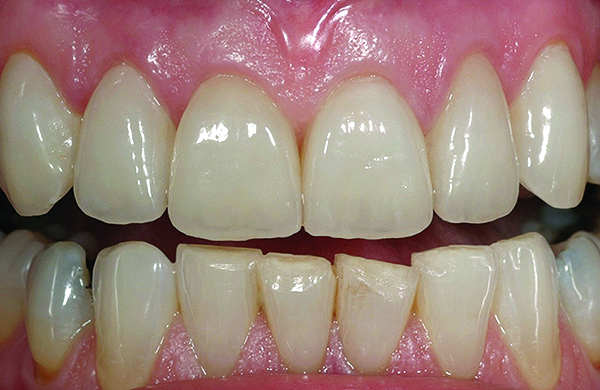

Class I (CL-I) powder and liquid porcelains are created from materials primarily containing silicon dioxide and possess a glassy matrix and varying amounts of a crystalline phase within the glassy matrix (eg, Creation Porcelain, Jensen Dental, www.jensendental.com; Ceramco 3, DENTSPLY International, www.dentsply.com; EX-3, Kuraray Noritake Dental, Inc, www.kuraraynoritake.com). The CL-1 group includes feldspathic porcelains, referred to as such because they were originally—and some continue to be—made from naturally occurring feldspars (ie, aluminosilicates composed of assorted quantities of potassium, sodium, barium, or calcium).9,17 Several feldspathic material options are available on the market today (eg, VITA VM 13, VITA Zahnfabrik, www.vita-zahnfabrik.com; Vintage Halo, Shofu, www.shofu.com) (Figure 1 through Figure 3).

CL-I materials are fabricated by hand (Figure 4); they are the most conservative and generally the most translucent ceramic materials, but they are also the weakest.9,10,18 The material’s high translucency and esthetics create the illusion of natural teeth.9 Powder/liquid porcelain materials are ideal for cases in which significant enamel remains and/or there is healthy tooth structure on the teeth (ie, 50% or more remaining enamel on the tooth, 50% or more of the bonded substrate is enamel, and 70% or more of the margin is in the enamel). Feldspathic porcelain restorations that are bonded to primarily enamel substrates have proven to be highly successful long term.19

Powder/liquid porcelains demonstrate high esthetics and workability, and because they can be layered very thinly and placed directly on the enamel, they are considered the most conservative of the metal-free ceramic classes.10 CL-I porcelains require a thickness of 0.2 mm to 0.3 mm for each shade change.20,21

Figure 1 Preoperative, preparation, and final postoperative images of a 2-unit CL-I feldspathic veneer case.

Figure 1

Figure 2 Preoperative, preparation, and final postoperative images of a 2-unit CL-I feldspathic veneer case.

Figure 2

Figure 3 Preoperative, preparation, and final postoperative images of a 2-unit CL-I feldspathic veneer case.

Figure 3